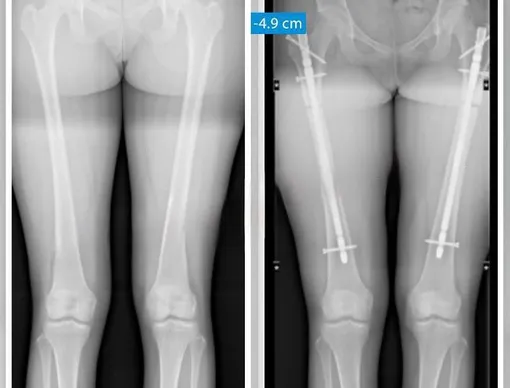

Чтобы добиться нужного результата, врачи спиливают часть бедренной или большеберцовой кости. Это позволяет уменьшить рост на 3–5,5 см. Так, к примеру, одна из обратившихся пациенток добилась того, что её рост снизился со 172 до 167 см.